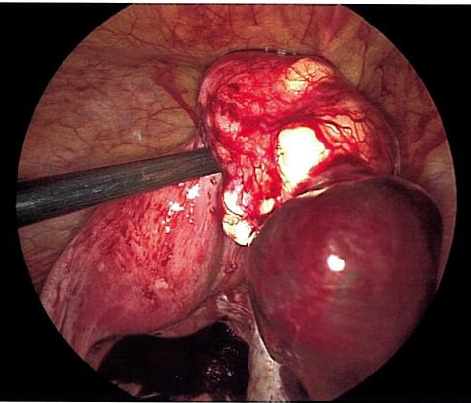

The patient was taken urgently to the operating room for diagnostic laparoscopy due to concern for right adnexal ectopic pregnancy. Upon entry into the abdomen, hemoperitoneum was noted extending into bilateral paracolic gutters. Following removal of this clot, a ruptured ectopic pregnancy was identified at the inferior pole of a 4 cm pedunculated fibroid arising from the posterior fundal surface of the uterus with active bleeding (Figure 2). This ectopic pregnancy revealed no involvement of bilateral adnexa. Pelvic survey revealed normal bilateral fallopian tubes and ovaries. The pedunculated fibroid and ectopic pregnancy were resected with the Ligasure impact device and removed from the abdomen by two separate Endocatch bags. The base of the myomectomy (Figure 3) was oversewn with 2-0 vicryl for additional hemostasis.